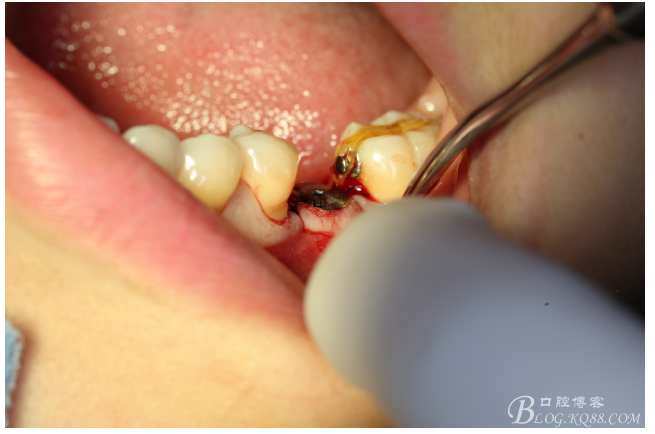

檢查:36.46缺失,36缺牙區(qū)近遠(yuǎn)中間隙約3mm,46缺牙區(qū)間隙約0.5mm,37.47.48近中傾斜,48近中面齲壞達(dá)牙本質(zhì)淺層,37牙周探診4mm,47近中探診深度5-6mm,不松,口內(nèi)照片及CT片如下:

口內(nèi)照片

處理:必蘭麻局部麻醉切開(kāi)37遠(yuǎn)中牙齦,植入mini支抗釘一枚,37近中鄰面粘舌側(cè)扣,皮鏈輕力牽引,3周更換。